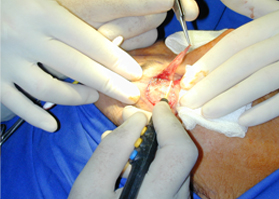

全新SURGITRON DUAL RF 120IEC,擁有更美的外觀,更強(qiáng)的性能,優(yōu)越的射頻止血功能,作為同時(shí)擁有4.0 Mhz和1.7Mhz的雙射頻產(chǎn)品,能應(yīng)用于更多的科室手術(shù)。